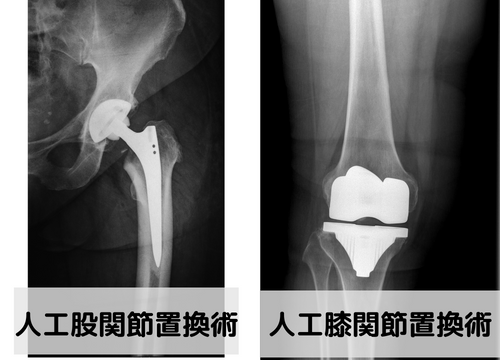

変形性股関節症、変形性膝関節に対する手術として代表的な手術として人工関節置換術があります。

この人工関節置換術は関節を丸ごと人工物に変える手術となります。

THAとは人工股関節置換術、TKAとは人工膝関節置換術の事です。